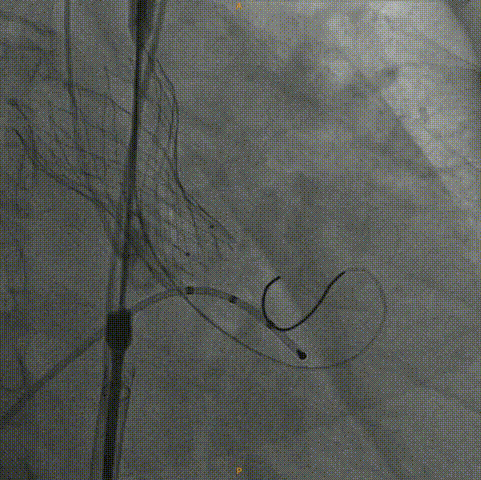

术中影像:

主动脉根部造影:左右冠灌注情况良好,瓣叶活动度一般,无明显反流。

20mm球囊预扩:冠脉灌注情况良好,瓣上结构改变,微量反流。

Venus26号瓣膜定位:结合瓣上结构考虑,采用0位释放。